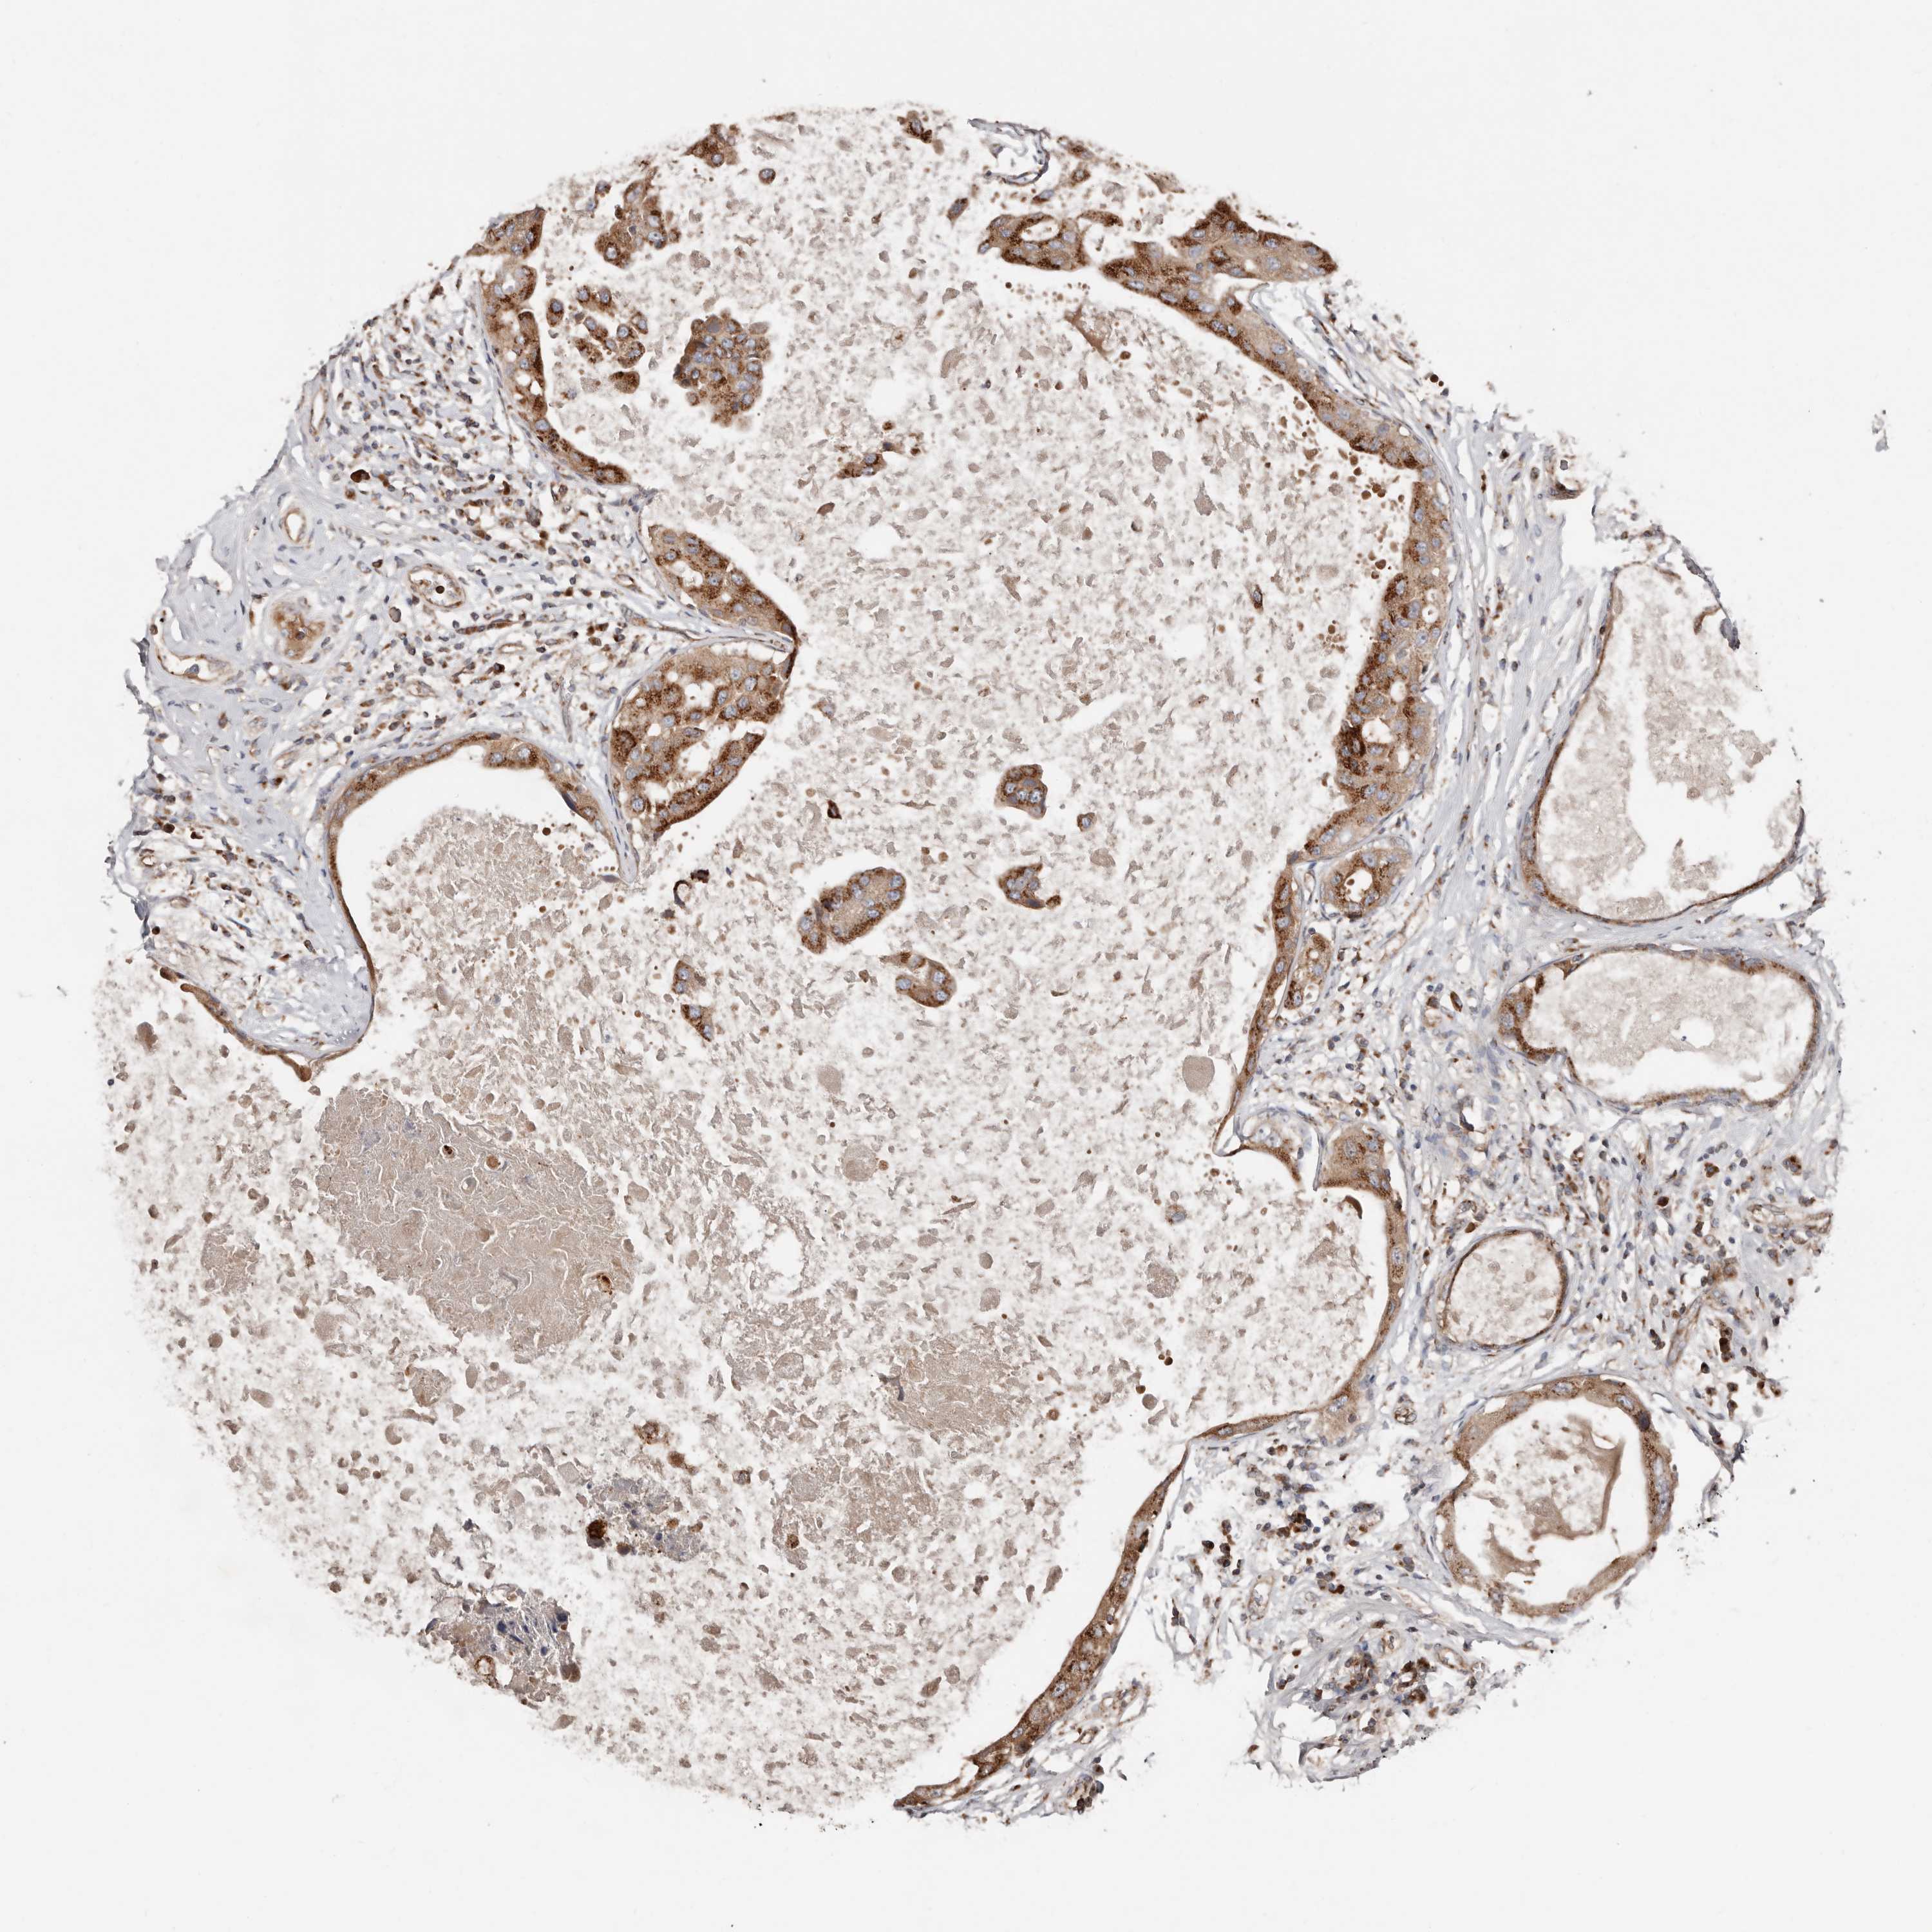

CANCER BREAST CANCER Show tissue menu

BRCA TCGA BRCA VALIDATION PROTEIN EXPRESSION